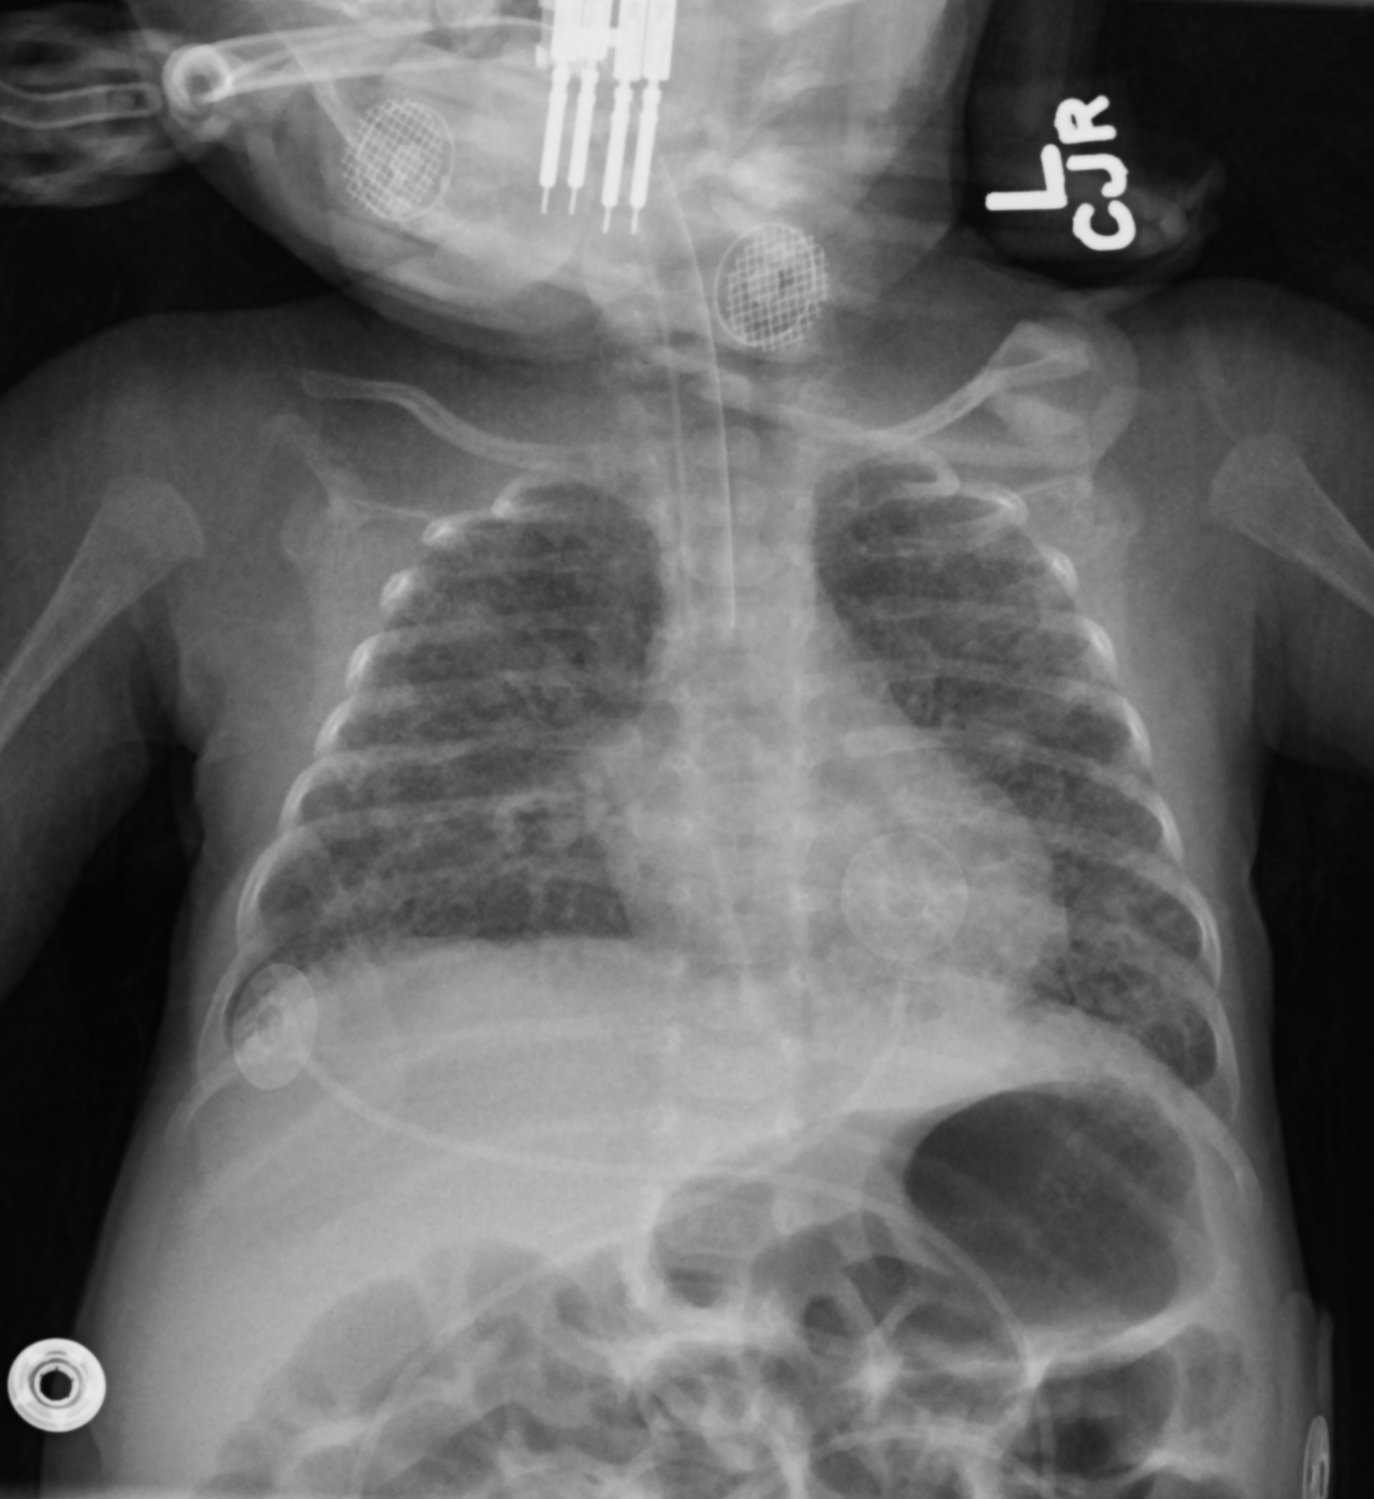

Meconium Aspiration Syndrome

• Diffuse bilateral coarse/rope like capacities

• If effusion present —> question PNA

• Eval for pneumothorax and pneumomediastinum (increased alveolar tension from obstructed airway)

• Increased lung volumes (hyperinflated)

• then they pop hence the pneumo

• Look for hypoxic baby

• Look for post-term baby